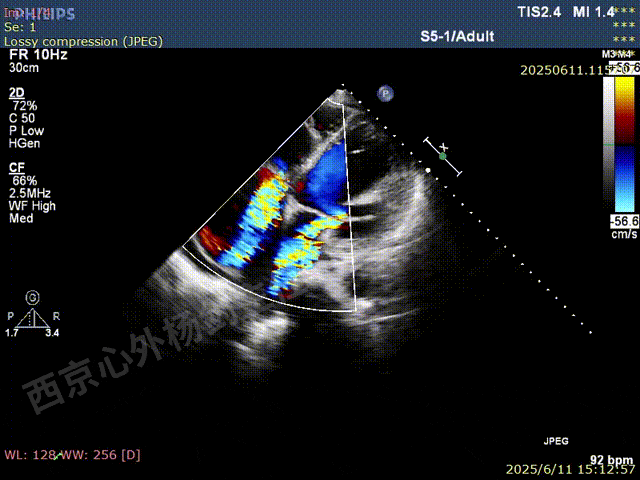

TAVR术后,全心增大,二尖瓣反流重度,三尖瓣反流重度。中量心包积液。左室严重增大,标准图像调整困难。主动脉瓣位带支架人工瓣膜瓣叶启闭正常,主动脉瓣位人工瓣上血流速度Vmax 148cm/s,PGmax 9mmHg,Vmean 86cm/s,PGmean 2mmHg, VTI 34.7cm,瓣周反流(轻)。估测肺动脉收缩压约49mmHg;左室收缩功能明显减低。LVEF:23%,EDV:364ml,ESV:221ml。

彩色血流示:二尖瓣反流缩流颈彩宽6.6mm,面积17cm²,容积30ml;二尖瓣瓣口面积6.6cm²,瓣环内径:左右径34mm,前后径34mm。2区瓣叶长度:前叶36mm,后叶20mm,叶环比1.6. 三尖反流面积17.2cm²,容积33ml,Vmax 291cm/s,PGmax 34mmHg。

二尖瓣后叶栓系严重,前叶相对错位,反流束沿2区分布广泛,2偏3区处存在反流。

反流宽度至少23mm,因影像调整困难,考虑实际反流更宽。